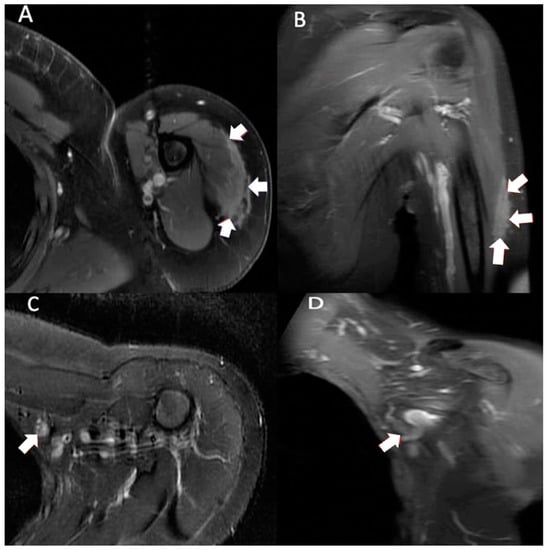

Figure 2. Multiplanar MRI of left shoulder taken 10 months after vaccine administration in left shoulder. Axial T1 weighted (A) image shows predominately intramuscular edema within the lateral deltoid muscle measuring 5.6 cm anterior-posterior and 1.0 cm medial-lateral (arrows). Coronal T1 weighted (B) image shows intramuscular edema within the lateral deltoid muscle measuring 10.0 cm proximal-distal (arrows). Axial T2 STIR (C) and coronal T1 weighted (D) images show a slightly enlarged left axillary node (9.9 × 11.2 × 12.8 mm) (arrows).

Three months after visiting the initial orthopedist, the patient attended a different orthopedic clinic to address the masses. At this visit, 10 months had passed since receiving her injections and the clinical examination showed normal range of motion with no tenderness to palpation. There were no rashes on inspection; however, edema and nodules to palpation were found in the lateral deltoid heads. Due to the persistent, previously unimaged left shoulder swelling, an MRI was performed, which showed similar findings of edema but in an intramuscular rather than subcutaneous location and the presence of a slightly enlarged axillary node (Figure 2). Ultimately, no biopsy or treatment was recommended on either side given the imaging findings and the improvement, albeit slow, in her symptoms and the swelling bilaterally. The patient’s symptoms had fully resolved when she returned after 2 months (1 year after completing the injections). Examination showed 5/5 deltoid strength bilaterally, full active range of motion without discomfort or crepitus, no visual deformities (swelling, effusion, erythema) in the distal upper extremities, and no joint tenderness on palpation.

Injection site granulomas were attributed to improper injection technique [15]. The intended location for COVID vaccination is intramuscular (IM), usually into the bulk of the deltoid muscle [5]. Injection site granulomas tend to occur in subcutaneous tissue (SC) and more frequently in females [15]. The depth of vaccine injections has a strong impact on tissue reaction. Deep IM injections are typically associated with fewer symptoms compared to SC or intradermal injections, possibly due to lower levels of nociceptors in muscle spindles compared with subcutaneous tissue and skin [16]. This likely accounts for the lower amount of swelling and pain on the patient’s left shoulder, where the imaging showed the reaction to be intramuscular, in contrast to the more symptomatic right shoulder subcutaneous reaction.